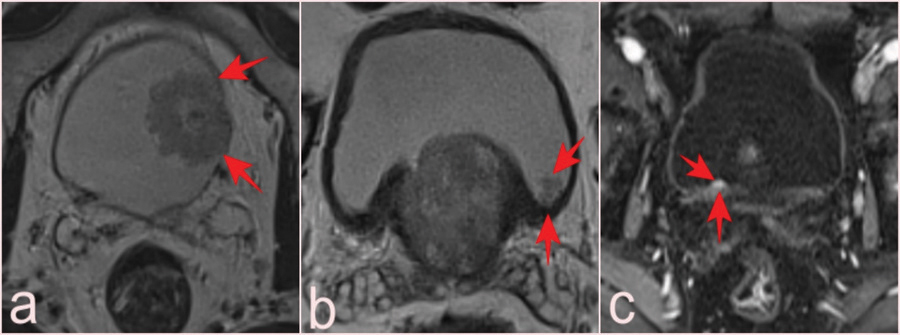

Figure 6

(a) T2-WI shows a VI-RADS 2 lesion with a high-grade pT1 tumor in a 74-year-old patient (arrows). (b) In a 60-year-old patient, a T2-WI image revealed a VI-RADS 1 lesion, 0.8 cm, missed without careful left posterior wall examination; pathology was pTa tumor (arrows). (c) VI-RADS 1 lesion, 0.6 cm, on the right posterior wall of a 74-year-old patient; contrast-enhanced DCE images aid selection; pathology: pTa tumor (arrows).